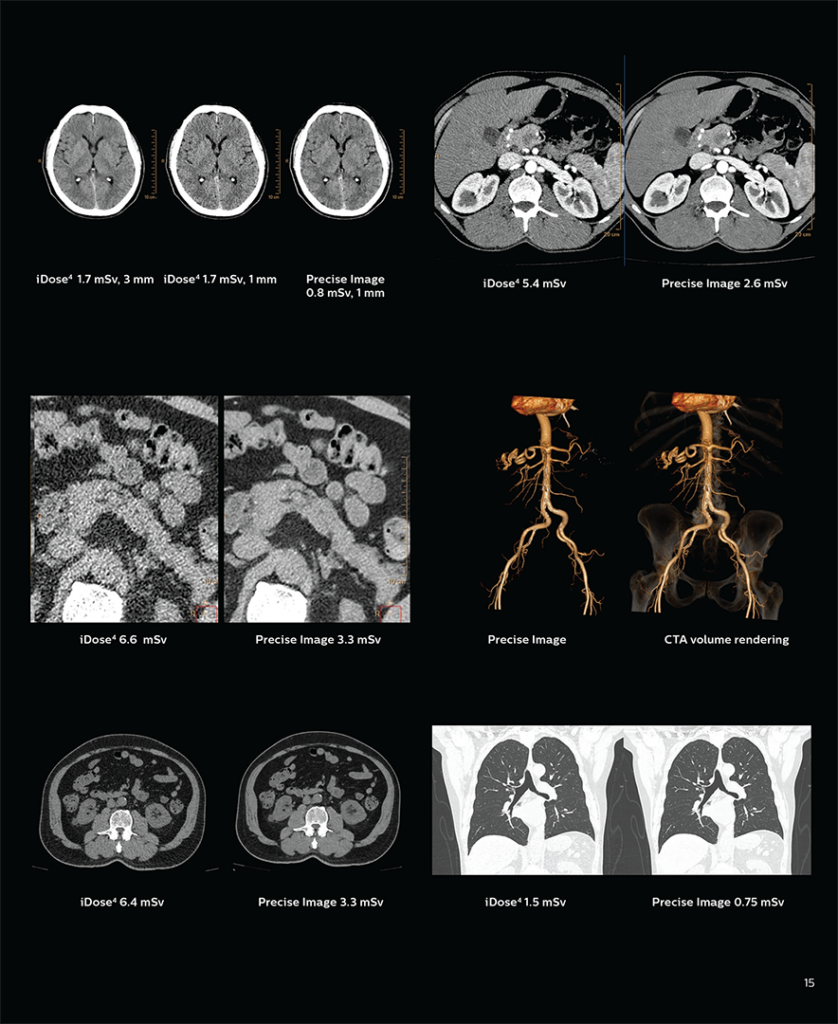

Gelişmiş yapay zeka (AI) rekonstrüksiyon teknolojisi ile daha hassas görüntü kalitesi ve azaltılmış okuma süreleri ile yüksek ve güvenli tanı imkanı sunan “Philips incisive ct 128 Slice” cihazı ile Tomografi çekiminde sizlere en kaliteli hizmeti sunuyoruz.